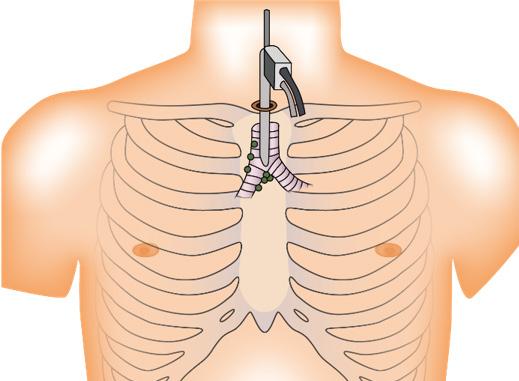

Tratamiento

Toracostomía / drenaje torácico con tubo torácico de 28 a 32 French (Toracotomía mínima cerrada) (ESSALUD 2018) → a nivel del quinto espacio intercostal con la línea axilar anterior o media (triangulo de seguridad)

Figura 13. Toracostomía → colocación de tubo de drenaje torácico (ESSALUD 2018) Figura 14. Toracotomía abierta